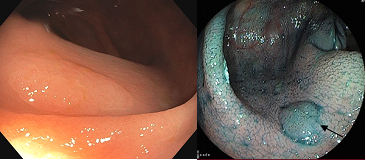

• De par sa fréquence, le dépistage du cancer colorectal (CCR) est incontournable. Le CCR est un cancer de bon pronostic quand il est diagnostiqué à un stade précoce. Le taux de survie à 5 ans dépend de la classification TNM (stade 1 : 94 %, stade 2 : 80 %, stade 3 : 47 %, stade 4 : 5 %). : Sauf terrain à risque particulier (maladies inflammatoies, lynch-HNPCC, FAP), la séquence adénome-cancer est présente dans 70 % des cas (figure 4). Le dépistage est efficace. La transformation d’un polype bénin en cancer prend environ 10 ans, expliquant le délai de surveillance entre deux procédures. A titre individuel, le gold standard reste la colonoscopie classique. La colonoscopie virtuelle est possiblement moins performante pour les polypes plans festonnés du côlon droit (plus à risque de cancérisation) (figure 5) mais peut être proposée aux patients à haut risque anesthésique ou sous anticoagulants. Un rythme de suivi endoscopique doit être respecté. En l’absence de guidelines belges, ce sont les guidelines européens qui doivent être appliqués (figure 6). Cette classification scinde les patients entre groupe à faible risque (endoscopie tous les 10 ans) et haut risque (endoscopie tous les 3-5 ans) selon les caractéristiques des polypes réséqués lors de la première colonoscopie.

Figure 5 : Adénome festonné